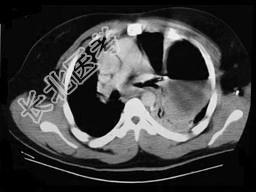

- 单项选择题35岁,男, 因车祸入院,呼吸困难、发绀、上腹痛, 请结合胸片和CT选择最可能的诊断 ( )

A、膈疝

B、胸腔积液

C、膈膨升

D、膈麻痹

E、液气胸